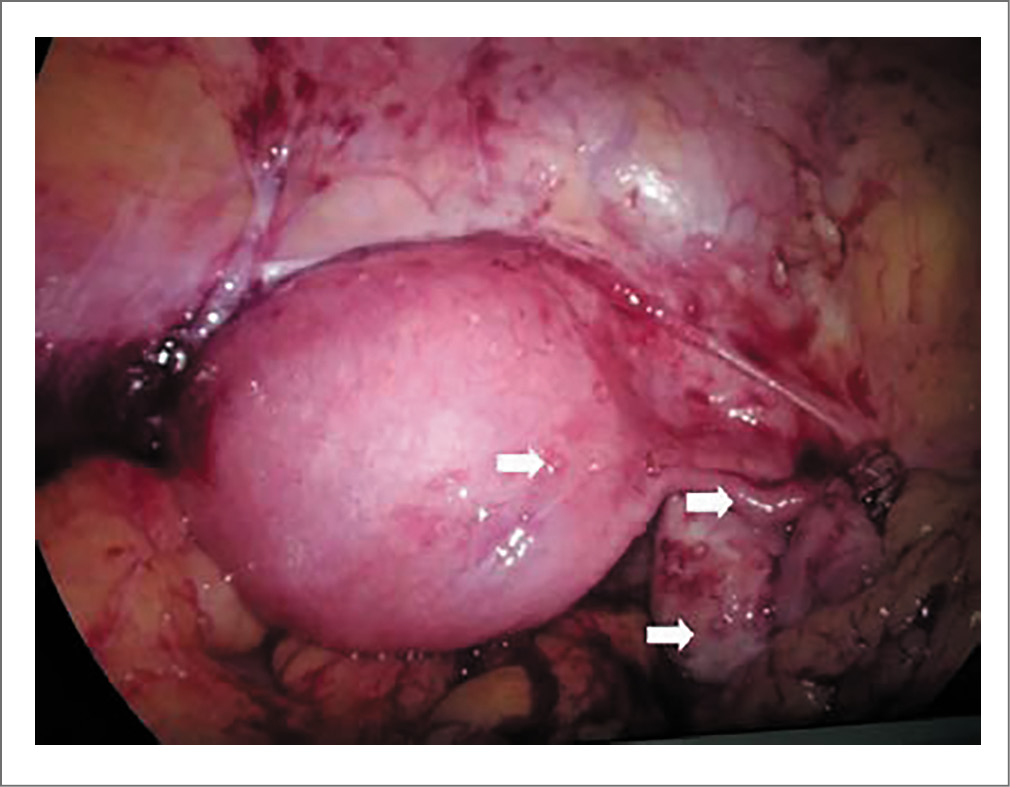

Типичная лапароскопическая картина при ТЖПО представлена на рис. 3, 4.

Рис. 4. ТЖПО, казеомы в дугласовом пространстве (одиночная стрелка) и на брюшине (двойная стрелка). Источник: J. Sharma и соавт. [29]. / Fig. 4. FGT, caseomas in the Douglas space (single arrow) and on the peritoneum (double arrow) [29].